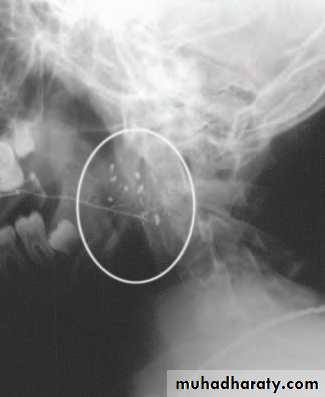

Stone formation (sialolithiasis) and stricturesParotid sialolithiasis 20%

The stones are usually radiolucent.

Locations; confluence of the collecting ducts, at the point the courses over the masseter muscle or in the distal aspect of the parotid duct adjacent to the parotid papilla.

Presentation: intermittent swelling particularly in the mealtimes.

Ix : US